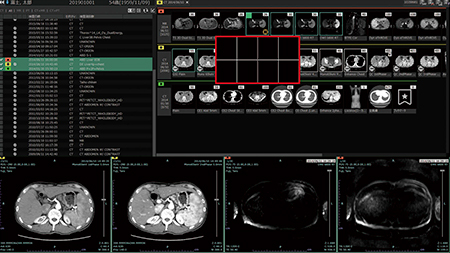

ユーザーインターフェイスなど読影基本機能が進化

SAI viewerでは,読影ビューワとしての基本機能が進化しているのも特長だ。読影時の操作をサポートする機能として,必要な検査をワンクリックで絞り込める“モダリティ種別フィルタ”や,検査リストの表示領域を拡張して選択できる機能などを搭載する。また,“クイックレイアウト機能”では,リストで選択された検査のサムネイル画像のすぐ下に,ビューワの割り当て場所を示す枠が表示され,その枠にドラッグ&ドロップすることでビューワ画面に反映される。マウスを大きく移動させずに検査画像のレイアウティングが行える。菊地医師はクイックレイアウト機能について,「最小限のマウスの移動で,見たい場所に画像を表示できるので便利です」と評価する。

クイックレイアウト機能

クイックレイアウト(赤枠内)はシリーズのサムネイル画像のすぐ下にビューワの表示場所を示すグリッドが表示され,ここにドラッグ&ドロップすることで最小のマウス操作で画面レイアウトができる。